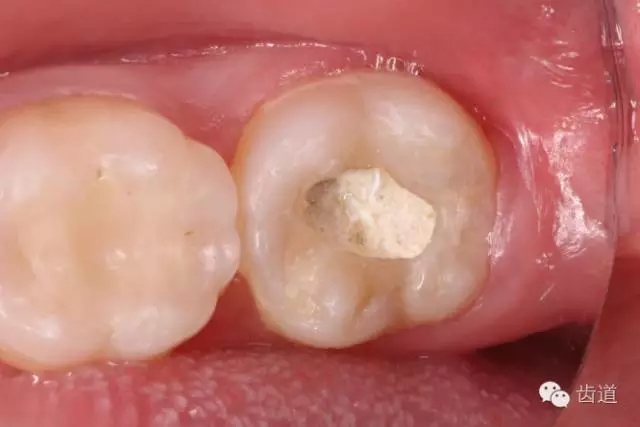

10. 術(shù)后即刻口內(nèi)照片